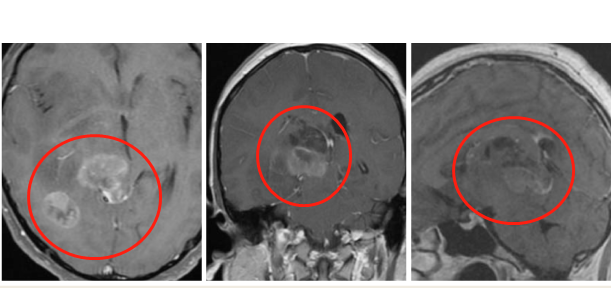

術后影像(多發(fā)性膠質母細胞瘤)

術后情況:

術后一天患者清醒,可用英語正常對答;術后三天即遷出ICU;術后一周可在家屬摻扶下床并進行康復鍛煉;術后一個月,恢復情況較好,可自行步行出院。左側肢體肌力5-級,左下肢仍可見跛行狀,左上肢細致活動仍較差,但已能自行持筷用餐,癲癇再未發(fā)作。術后病理結果顯示為膠質母細胞瘤WHO IV級。